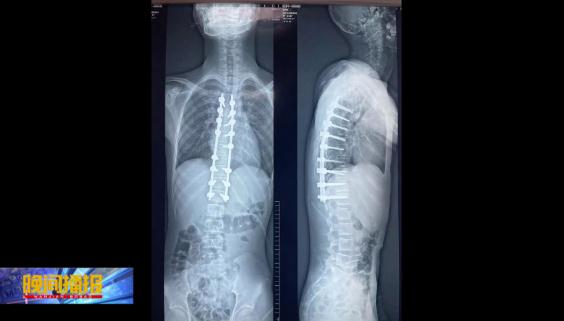

在中国科大附一院(安徽省立医院)南区多科室的密切配合下,近日,张文志带领团队为乐乐进行了机器人导航辅助下脊柱侧弯三维矫形内固定术。术后乐乐身高也增加了2厘米,经过一个月的休养,目前已经回到校园。